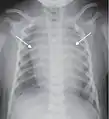

Chest radiograph

A normal posteroanterior (PA) chest radiograph of someone without any signs of injury. Dx and Sin stand for "right" and "left" respectively.